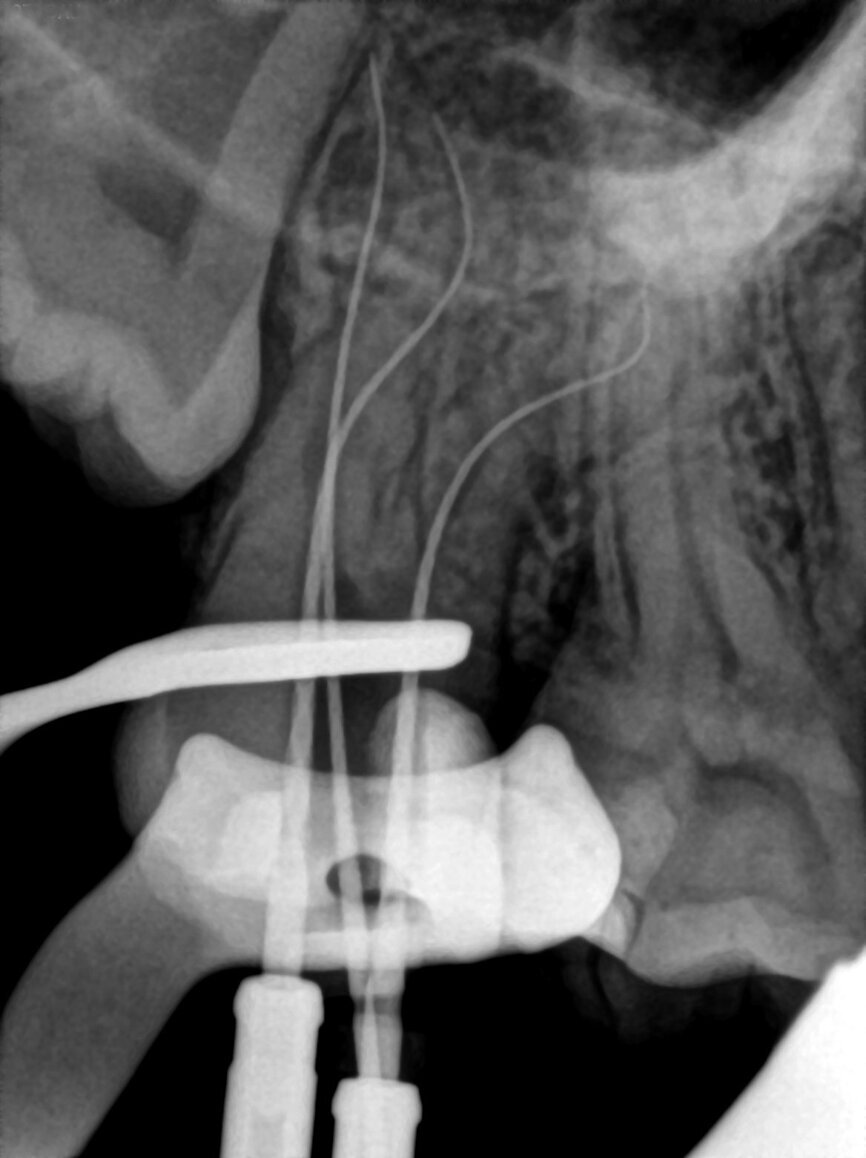

Fig. 20: Length determination radiograph.

The pulp chamber was filled with Glyde (Dentsply Sirona) before the canals were carefully negotiated to full working using pre-curved size 08 K-Files (Fig. 19). Working length measurements obtained from an electronic apex locator reading corresponded with the lengths obtained from the 3D Endo Software. These measurements were also confirmed radiographically (Fig. 20). A reproducible glide path was prepared in each root canal system with the size 08 K-File in an M4 Reciprocating handpiece (Sybron Endo; Fig. 21), followed by making a size 10 K-File ‘super loose’ (Fig. 22). A ProGlider (Dentsply Sirona) was used in a rotary motion to expand the glide path in the palatal root canal (Fig. 23). Considering the sharp and severe curvatures in the two buccal canals, it was decided to convert the ProGlider instrument into a manual file to expand the glide path in these tortuous canals with more safety (Fig. 24). The manually adapted ProGlider was used in a balanced force motion up to working length. In addition, to create more safety during the canal preparation of the two challenging buccal root canals, it was also decided to use the reciprocating WaveOne Gold Glider (Dentsply Sirona; Fig. 25), after the ProGlider instrument to further expand the glide paths. The WaveOne Gold Glider was used in 4–8 backstroke brushing motions from working length, in the two buccal root canal systems.